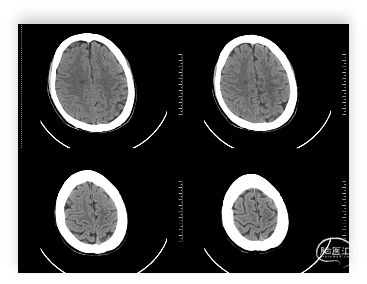

头颅MRI:左侧额顶叶急性脑梗塞;桥脑左份、双侧基底节、右侧脑室旁及双侧额叶多发腔隙性脑梗塞;双侧脑室旁及额顶叶轻度白质脱髓鞘;双侧上颌窦、筛窦、蝶窦炎;脑MRA示①右侧椎动脉纤细(变异)②左侧大脑后动脉P2段局部狭窄③左侧颈内动脉眼段局部严重狭窄④脑动脉轻度硬化改变,请结合临床及其他检查协诊。

诊断依据:1、老年男性,静态起病。2、查体右侧肢体肌力5级差,右侧病理反射阳性。3、头颅MRI示:左侧额顶叶急性脑梗塞。